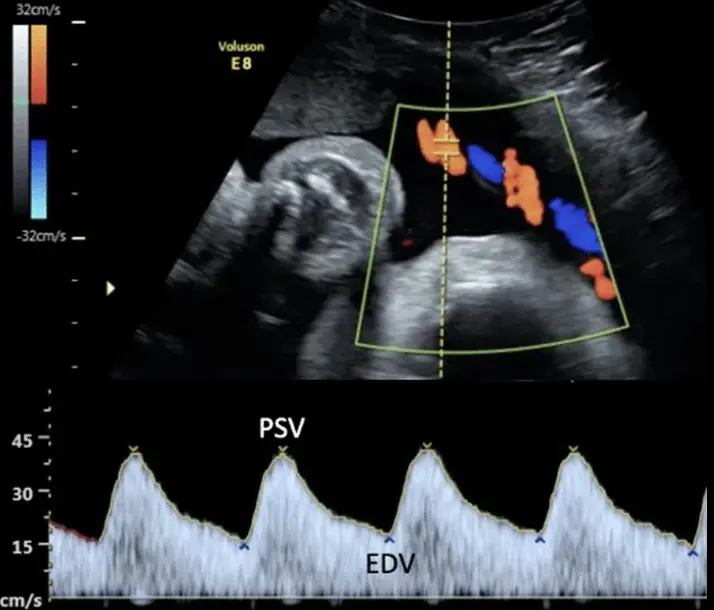

A third trimester ultrasound is an ultrasound scan performed during the final stage of pregnancy, typically after 28 weeks. It is usually recommended when there is a medical reason to assess the baby’s wellbeing, growth, or position. Unlike the routine scans performed earlier in pregnancy, not everyone will need a third trimester ultrasound unless advised by their healthcare provider.

A third trimester ultrasound may be recommended if there are concerns such as reduced fetal movements, high or low levels of amniotic fluid, abnormal fundal height (the size of your belly), maternal medical conditions (like high blood pressure or diabetes), previous pregnancy complications, or if the baby is suspected to be too small or too large for gestational age.

The main purpose of a third trimester ultrasound is to check how your baby is growing and developing. It allows the sonographer to measure your baby’s size, monitor growth over time, and assess the amount of amniotic fluid around the baby. The position of the baby (whether head-down, breech, or transverse) and the location and appearance of the placenta are also checked. Blood flow in the umbilical cord and other vessels may be assessed using Doppler ultrasound if there are concerns about the baby’s growth or overall health.

You do not usually need a full bladder for this scan, and no special preparation is required. The scan usually takes around 20 to 30 minutes, but this may vary depending on the baby’s position and the specific reason for the ultrasound. You can typically bring a partner or support person with you.